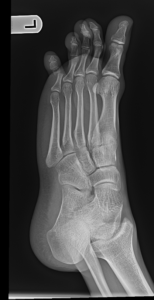

- Foot Fractures.